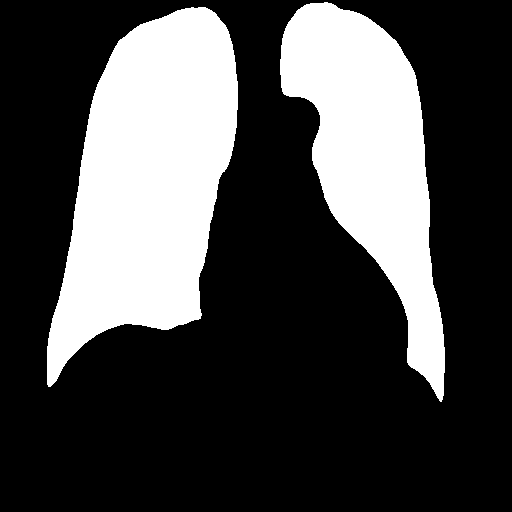

After heart and lung masks are computed, we performed dilation followed by erosion to fill holes in output mask [18], then we find the connected components of prediction masks (Figure 3).

From the lung mask, we chose the two largest connected components and disregarded others as noise. The connected component with a lower x-axis coordinate is designated as the left lung mask and the other as the right lung mask. From the heart mask, we chose the connected component larger than a given threshold and closest to the center and designate it as the heart mask.